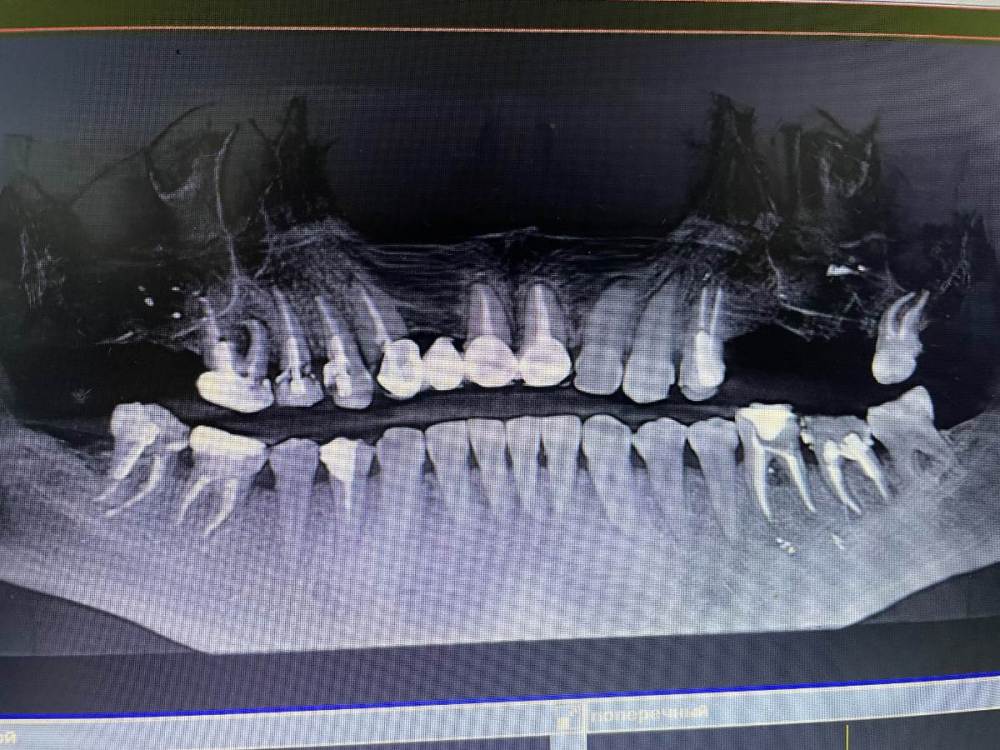

Amparo743 Опубликовано 21 октября, 2021 Поделиться Опубликовано 21 октября, 2021 Здравствуйте, уважаемые доктора. Прошу вашей помощи и мнений. Пришла к хирургу по поводу имплантации - трех верхних зубов 5,6,7, сделали 3d снимок. Врач сказал, что требуется удалить ещё 4 зуба и соответственно поставить туда импланты. Зубы жевательные, многострадальные и леченные - он говорит, что есть инфекция, которая никуда после лечения не делась и соответственно они подлежат удалению - так как может в любой момент начаться воспаление. То есть он предлагает удалить верхнюю 6 слева, нижнюю 6 слева, и нижние 6 и 7 справа. Сначала поставить импланты вверху с синус лифтингом, потом через 3 месяца провести удаление трех нижних зубов с единовременной установкой имплантов. И потом через 6 месяцев выйти к единовременному протезированию всех имплантов. Пришла по отзывам в интернете. Живу в небольшом городе. Выбор не велик. Врач вызвал доверие. Но конечно хотелось бы узнать ещё мнения. У меня был постоянный лечащий врач, которому я доверяла (в прошедшем времени). В её клинике была возможность так же сделать снимок 3d, и она видела состояние моих зубов и сама же их и лечила. И при каждом посещении настаивала на установке коронок на пломбы. То есть полагала, что ещё можно заработать что эти зубы ещё могут пожить с коронками. А хирург говорит, что они однозначно под удаление. Почему так критично написала - так как недавно удаленная верхняя 7 была ей пролечена долго и дорого 11 месяцев назад и теперь благополучна удалена из-за воспаление в корне. То есть зуб изначально был обречен. Вопрос - По Вашему мнению действительно ли зубы подлежат удалению? Подойдут ли для моей ситуации импланты Osstem? Конечно по цене, учитывая количество подлежащих имплантации зубов, они меня более, чем устраивают. А как по качеству? Буду вам очень благодарна за ответы. Ссылка на комментарий

Irouil Опубликовано 21 октября, 2021 Поделиться Опубликовано 21 октября, 2021 Чтобы оценить прогноз перелеченных зубов надо увидеть ещё и снимки до лечения чтобы сравнить что было с тем, что стало. Такой вид снимка очень малоинформативен, я рекомендую либо выложить срезы из КТ интересующих Вас областей, либо выложить всю КТ 1 1 Ссылка на комментарий

Irouil Опубликовано 21 октября, 2021 Поделиться Опубликовано 21 октября, 2021 Можете попробовать скинуть КТ в терапевтической ветке, тут надо его хорошенько посмотреть у каждого зуба чтобы оценить шансы на перелечивание, да и снимки до лечения было бы неплохо увидеть - может там динамика к улучшению стремится, но пока, судя по тем срезам что я вижу, вероятнее всего зубы действительно нужно будет удалять. Ссылка на комментарий

Bier Опубликовано 21 октября, 2021 Поделиться Опубликовано 21 октября, 2021 воспаление есть, скорее всего хирург прав, еще одно перелечивание они не перенесут. Ссылка на комментарий